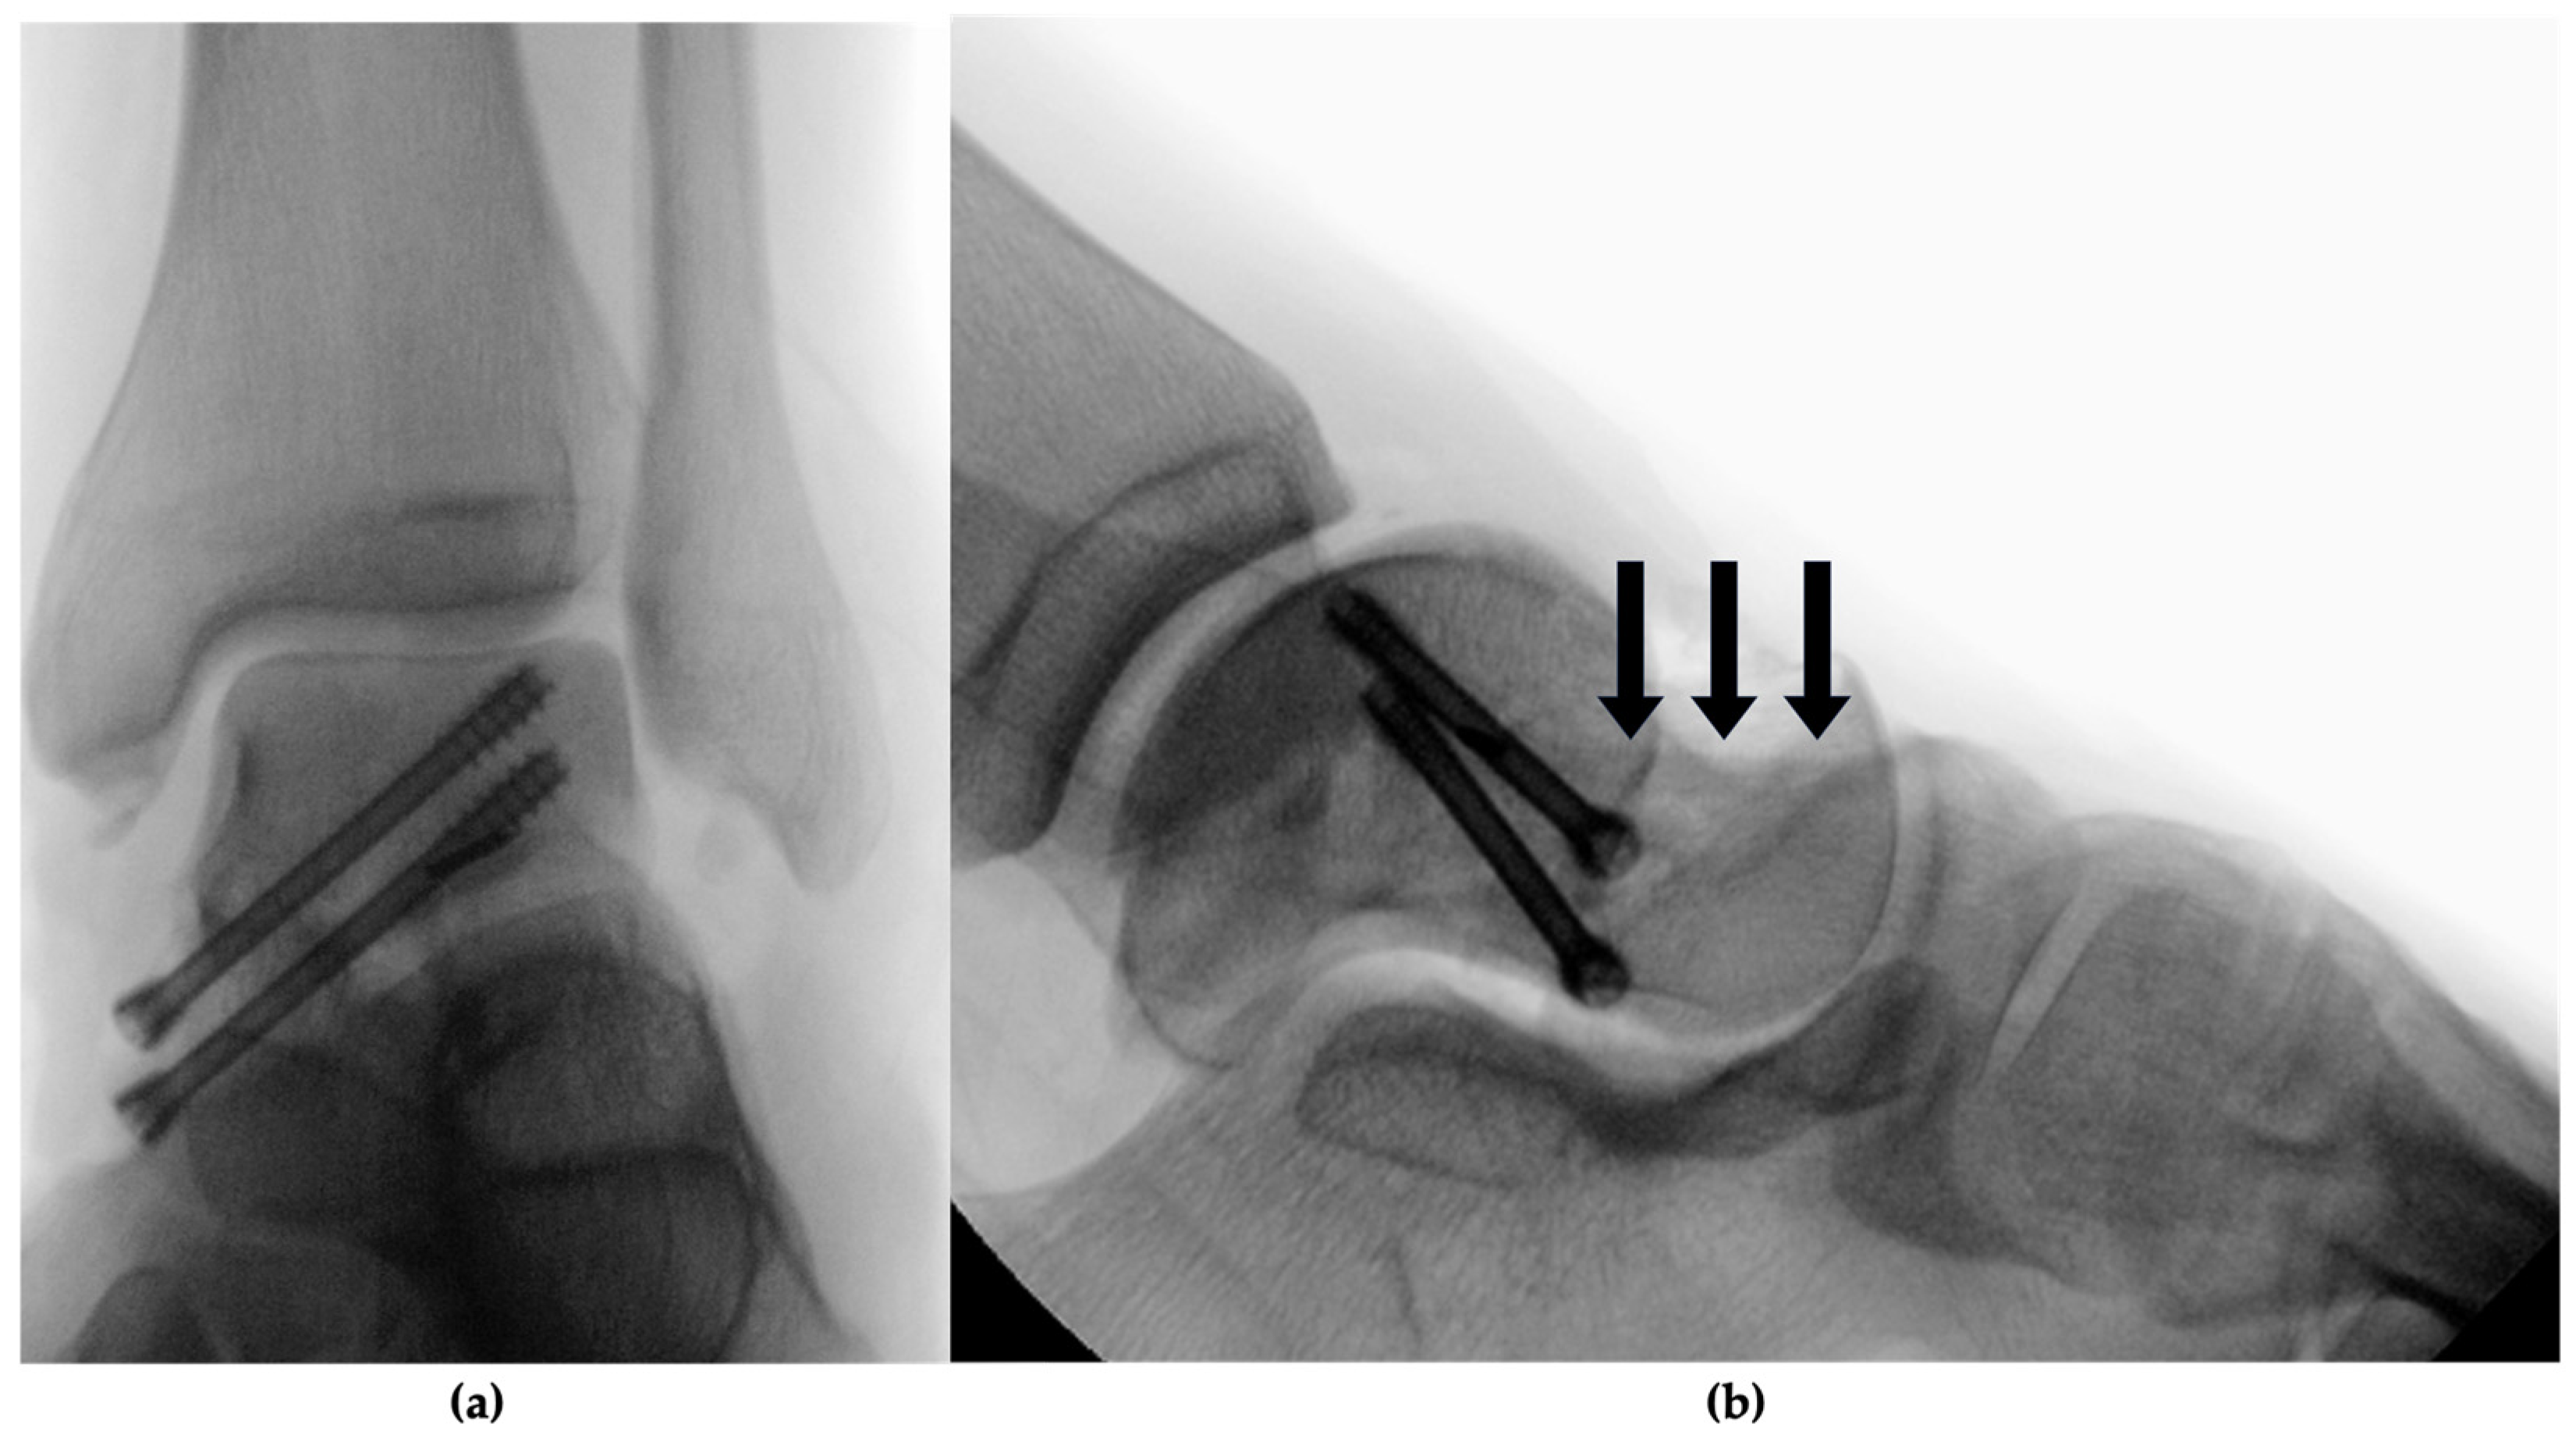

2.2. Therapeutic Intervention